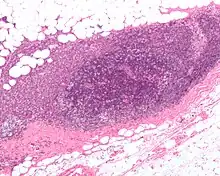

To perform a sentinel lymph node biopsy, the physician performs a lymphoscintigraphy, wherein a low-activity radioactive substance is injected near the tumor. The injected substance, filtered sulfur colloid, is tagged with the radionuclide technetium-99m. The injection protocols differ by doctor but the most common is a 500 μCi dose divided among 5 tuberculin syringes with 1/2 inch, 24 gauge needles. In the UK 20 megabecquerels of nanocolloid is recommended.[8] The sulphur colloid is slightly acidic and causes minor stinging. A gentle massage of the injection sites spreads the sulphur colloid, relieving the pain and speeding up the lymph uptake. Scintigraphic imaging is usually started within 5 minutes of injection and the node appears from 5 min to 1 hour. This is usually done several hours before the actual biopsy. About 15 minutes before the biopsy the physician injects a blue dye in the same manner. Then, during the biopsy, the physician visually inspects the lymph nodes for staining and uses a gamma probe or a Geiger counter to assess which lymph nodes have taken up the radionuclide. One or several nodes may take up the dye and radioactive tracer, and these nodes are designated the sentinel lymph nodes. The surgeon then removes these lymph nodes and sends them to a pathologist for rapid examination under a microscope to look for the presence of cancer.

A frozen section procedure is commonly employed (which takes less than 20 minutes), so if neoplasia is detected in the lymph node a further lymph node dissection may be performed. With malignant melanoma, many pathologists eschew frozen sections for more accurate "permanent" specimen preparation due to the increased instances of false-negative with melanocytic staining.